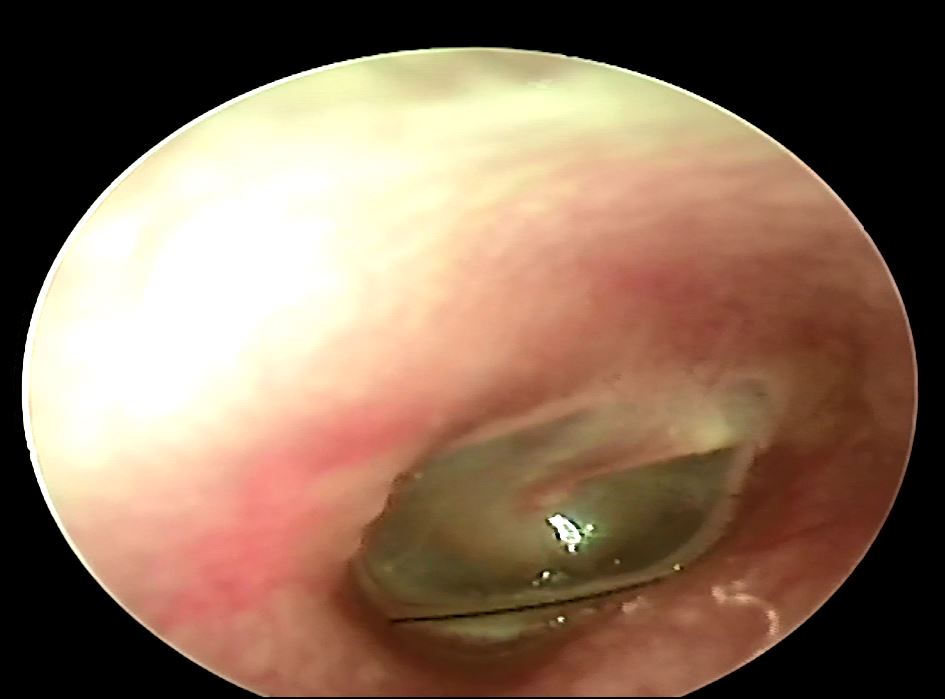

耳朵內的異物最難取出的是耳垢或是蟲子嗎? 答案都不是,最拿取出的其實是最微不足道的"頭髮"!! 而且是卡在最深處的頭髮,最近遇到一位病人一直覺得耳朵內有時會有怪聲合併輕微的耳悶,後來仔細一看原來是在耳膜上卡了一根頭髮,在內視鏡輔助下花了一點時間終於幫病人解決問題,有耳悶情形的話提醒大家可以到耳鼻喉科檢查一下喔!!